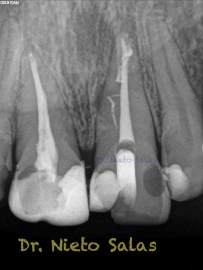

Una vez que hemos desbridado biomecánicamente con limas de muy pequeño diámetro, obturamos:

Y este sería el otro caso:

Es muy importante cambiar la proyección de las Rx para tener más información de como hemos sellado el sistema de conductos.